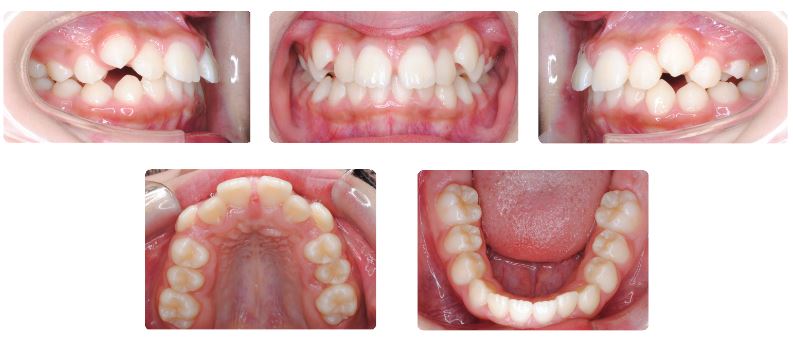

八重歯 (歯が重なり合っている状態 10代前半)

主訴:前歯の歯並び、特に上顎の犬歯の位置が気になる

初診時年齢:11歳

性別:女性

診断名:叢生

抜歯/非抜歯:非抜歯

装置名:マルチブラケット装置

治療費用:約62万円(税抜)と来院時に調節料5,000円(税抜)

治療期間:2年4ヶ月

治療に関する副作用/リスク:歯の移動時の痛み  装置による口腔粘膜の口内炎  カリエス

上あごの左右犬歯の位置が気になるとのことでご来院されました。

上あごの歯列の幅が狭いため、裏側に拡大装置を装着して広げながら前歯が並ぶスペースを確保していきます。

上あごの12才臼歯である第二大臼歯が生えてくるまで時間がかかったこと、上あごの奥行きがやや足りないため生え始めた際に頬側に向かい交叉咬合になってしまい、この噛み合わせの改善のために2年4か月を要しました。